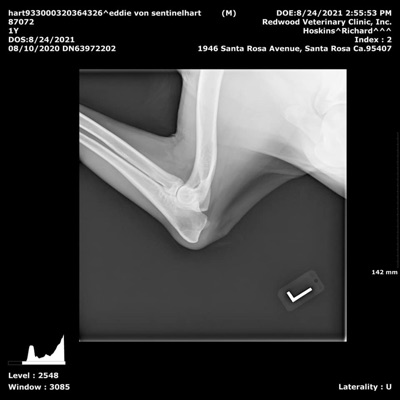

SV Hips A1

SV Elbows  Normal